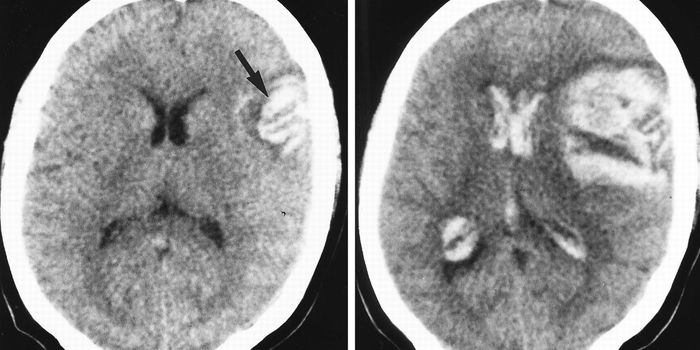

MAY 04, 2016NeuroscienceRupture of small blood vessels in the brain can cause hemorrhagic stroke and brain microbleeds, and finding the fastest ...